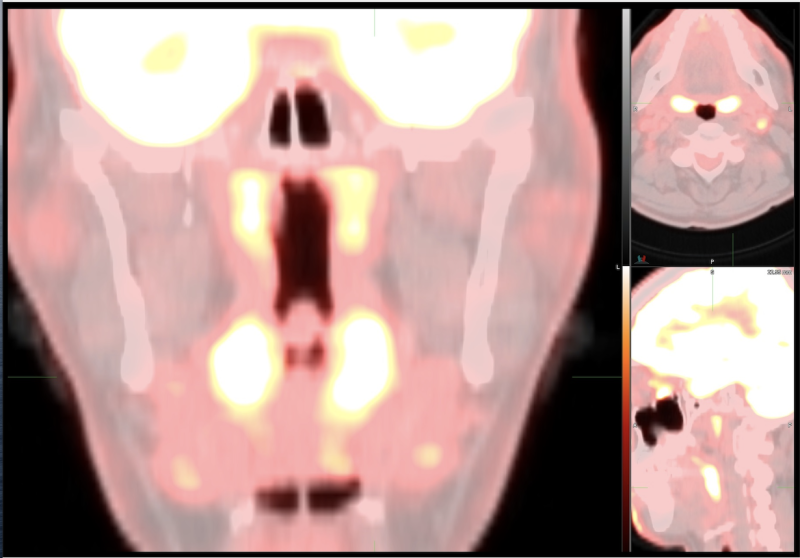

This photo gallery shows the variety of radiological presentations of COVID-19 (SARS-CoV-2) in medical imaging, including computed tomography (CT), radiograph X-rays, ultrasound, echocardiograms and magnetic resonance imaging (MRI). The radiology images show examples of typical COVID pneumonia in the lungs and the numerous complications the virus causes in the body in multiple organs, including the brain, kidneys, heart, abdomen and vascular system.

Ultrasound, especially hand-held ultrasound imaging devices, have become a primary imaging modality for novel coronavirus because of the ease to bag the device and sterilize it after use. CT and mobile X-ray systems are also used as front-line imaging systems for COVID-positive or suspected COVID patients.